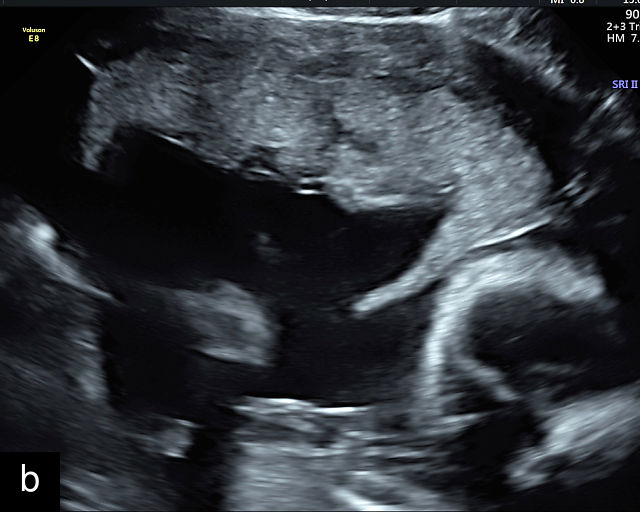

Normal ultrasound appearance of the placenta

Placental characteristics by trimester: thickness, echogenicity and location

In the early first trimester, trophoblastic tissue appears as an echogenic ring encircling the gestational sac (Figure 1a). By the late first trimester, the placenta becomes recognizable as a distinct structure on ultrasound (Figure 1b). Initially, it presents as a homogeneous echogenic mass (Figure 1b–d) but undergoes progressive differentiation, becoming more heterogeneous as pregnancy advances from the second to third trimester (Figure 1e–g). By the third trimester, cotyledons become discernible, and in the late third trimester, calcifications frequently appear basally and around the cotyledons (Figure 1g).

1

Ultrasound images of development of the placenta (P/p). (a) Trophoblastic tissue appearing as an echogenic ring surrounding the gestational sac at 6 weeks' gestation. (b) Placenta at 12 weeks has become a discrete, uniformly echogenic mass. (c) Placenta at 17 weeks. (d) Placenta at 20 weeks. (e) Placenta at 27 weeks. (f) Placenta at 33 weeks. Increasingly, differentiation and heterogeneous appearance is seen, with demarcation of the cotyledons. Basal calcifications are beginning to appear. (g) Placenta at 40 weeks, showing a distinctly heterogeneous appearance, with clear demarcation of the cotyledons and presence of calcifications.